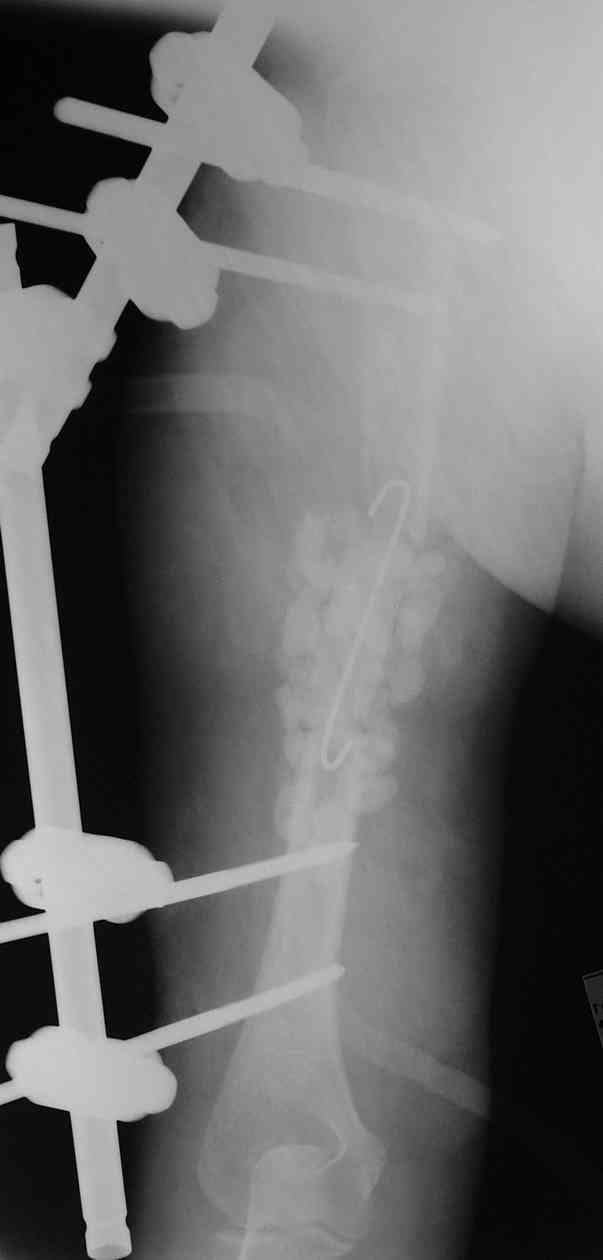

Такие надмыщелковые переломы в изолированном виде у нас в последние годы обычно фиксируются плоским титановым стержнем a la Зверев-Ключевский антеградно. Но тут еще и вышележащие проблемы.

Наверно, можно пойти на укорочение, убрав металлический цилиндр, не такой уж большой дефект. Снимки в чем-то похожего пациента прилагаю - тоже несращение диафиза после многократных операций, и надмыщелковый свежий перелом (случился после удаления обломка стержня аппарата).